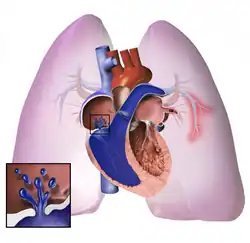

The pathogenesis of pulmonary arterial hypertension (WHO Group I) involves the narrowing of blood vessels connected to and within the lungs. This makes it harder for the heart to pump blood through the lungs, as it is much harder to make water flow through a narrow pipe as opposed to a wide one. Over time, the affected blood vessels become stiffer and thicker, in a process known as fibrosis. The mechanisms involved in this narrowing process include vasoconstriction, thrombosis, and vascular remodeling (excessive cellular proliferation, fibrosis, and reduced apoptosis/programmed cell death in the vessel walls, caused by inflammation, disordered metabolism and dysregulation of certain growth factors).[27][28] This further increases the blood pressure within the lungs and impairs their blood flow. In common with other types of pulmonary hypertension, these changes result in an increased workload for the right side of the heart.[16][29] The right ventricle is normally part of a low pressure system, with systolic ventricular pressures that are lower than those that the left ventricle normally encounters. As such, the right ventricle cannot cope as well with higher pressures, and although right ventricular adaptations (hypertrophy and increased contractility of the heart muscle) initially help to preserve stroke volume, ultimately these compensatory mechanisms are insufficient; the right ventricular muscle cannot get enough oxygen to meet its needs and right heart failure follows.[16][28][29] As the blood flowing through the lungs decreases, the left side of the heart receives less blood. This blood may also carry less oxygen than normal. Therefore, it becomes harder and harder for the left side of the heart to supply sufficient oxygen to the rest of the body, especially during physical activity.[30][31][11] During the end-systolic volume phase of the cardiac cycle, the Gaussian curvature and the mean curvature of the right ventricular endocardial wall of PH patients were found to be significantly different as compared to controls.[32]

In PVOD (WHO Group I), pulmonary blood vessel narrowing occurs preferentially (though not exclusively) in post-capillary venous blood vessels.[33] PVOD shares several characteristics with PAH, but there are also some important differences, for example differences in prognosis and response to medical therapy.[34]

Persistent pulmonary hypertension of the newborn occurs when the circulatory system of a newborn baby fails to adapt to life outside the womb; it is characterized by high resistance to blood flow through the lungs, right-to-left cardiac shunting, and severe hypoxemia.[16]

Pathogenesis in pulmonary hypertension due to left heart disease (WHO Group II) is completely different in that constriction or damage to the pulmonary blood vessels is not the issue. Instead, the left heart fails to pump blood efficiently, leading to pooling of blood in the lungs and back pressure within the pulmonary system. This causes pulmonary edema and pleural effusions.[35] In the absence of pulmonary blood vessel narrowing, the increased back pressure is described as 'isolated post-capillary pulmonary hypertension' (older terms include 'passive' or 'proportionate' pulmonary hypertension or 'pulmonary venous hypertension'). However, in some patients, the raised pressure in the pulmonary vessels triggers a superimposed component of vessel narrowing, which further increases the workload of the right side of the heart. This is referred to as 'post-capillary pulmonary hypertension with a pre-capillary component' or 'combined post-capillary and pre-capillary pulmonary hypertension' (older terms include 'reactive' or 'out-of-proportion' pulmonary hypertension).[13][18][36]

In pulmonary hypertension due to lung diseases and/or hypoxia (WHO Group III), low levels of oxygen in the alveoli (due to respiratory disease or living at high altitude) cause constriction of the pulmonary arteries. This phenomenon is called hypoxic pulmonary vasoconstriction, and it is initially a protective response to stop too much blood from flowing to areas of the lung that are damaged and do not contain oxygen. When the alveolar hypoxia is widespread and prolonged, this hypoxia-mediated vasoconstriction occurs across a large portion of the pulmonary vascular bed and leads to an increase in pulmonary arterial pressure, with thickening of the pulmonary vessel walls contributing to the development of sustained pulmonary hypertension.[11][37][38][39] Prolonged hypoxia also induces the transcription factor HIF1A, which directly activates downstream growth factor signaling that causes irreversible proliferation and remodeling of pulmonary arterial endothelial cells, leading to chronic pulmonary arterial hypertension.

In chronic thromboembolic pulmonary hypertension, or CTEPH (WHO Group IV), the initiating event is thought to be blockage or narrowing of the pulmonary blood vessels with unresolved blood clots; these clots can lead to increased pressure and shear stress in the rest of the pulmonary circulation, precipitating structural changes in the vessel walls (remodeling) similar to those observed in other types of severe pulmonary hypertension. This combination of vessel occlusion and vascular remodeling once again increases the resistance to blood flow, and so the pressure within the system rises.[40][41]